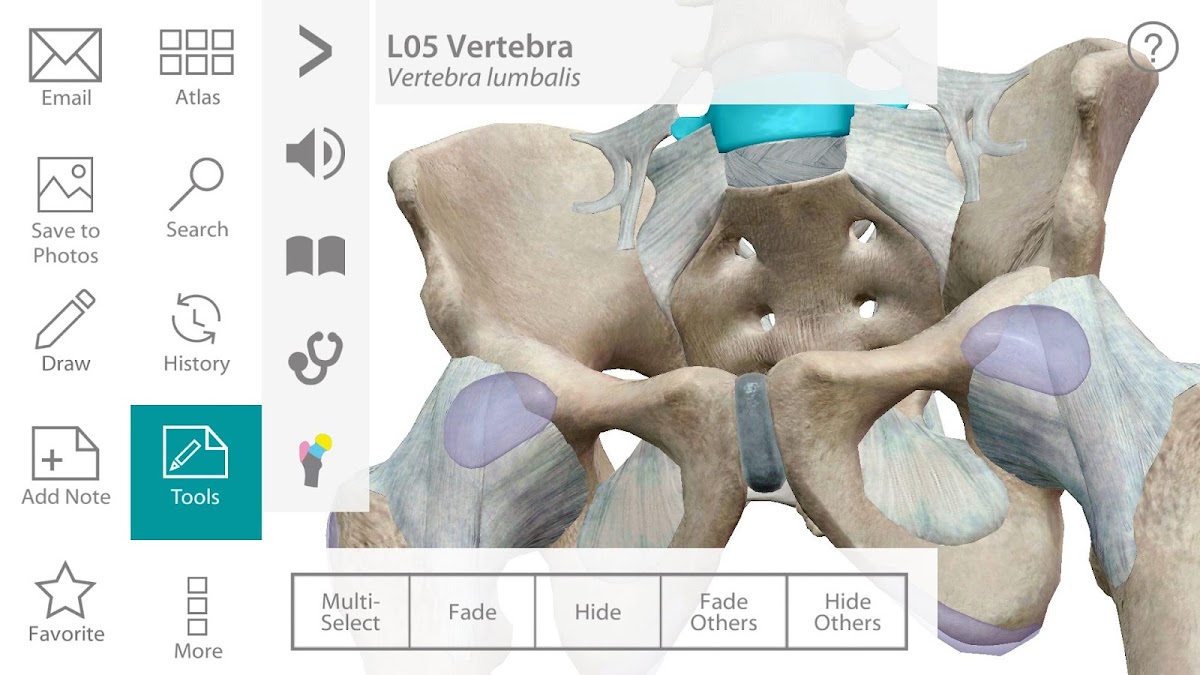

Human Anatomy Atlas

Visão Geral